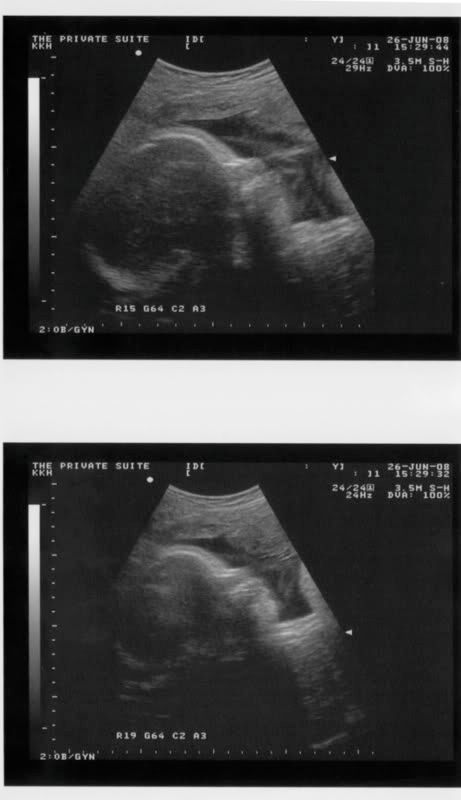

My gynae showed me my Princess's extremely chubby cheeks..So round!!! My gynae apologised for teasing my baby and told me that she will tease her more after she is born..Hehehe!!! Princess actually kicked the scanner thingy and made all of us laugh..Cheekly lil Princess.. :P

Her main concern today was Princess's weight..

So at 34 weeks, how much does Princess weigh?

2.4 kg..

Based on this,

Princess should weigh 2.1 kg!!

So after reviewing my condition, my gynae told DH and myself that Princess could weigh 3.2 - 3.4 kg by early Aug but if she is gaining too much weight, I may have to deliver her on end of July as my pelvis(based on my small frame) may not be big enough for her to pass through..

Princess's pics!!

Culmination of our love.. :*